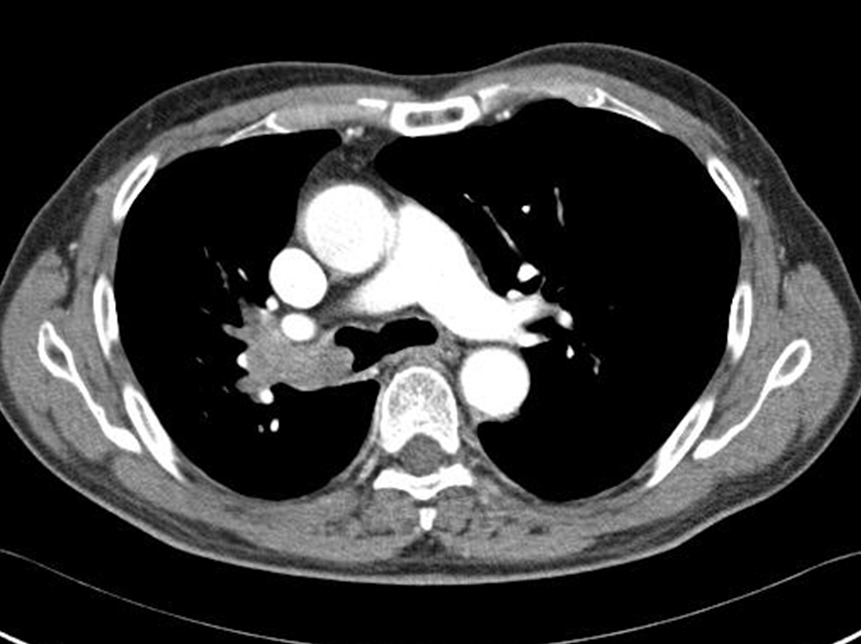

69 ¼¼ ³²È¯

CLL Áø´Ü¹Þ°í  allegenic stem cell transplantation ¹ÞÀº ÀÌÈÄ 8°³¿ù° ¹ß»ýÇÑ  ÇÑ´Þµ¿¾È Áö¼ÓµÇ´Â cough , Blood tingled sputum ÁÖ¼Ò·Î ³»¿øÇÔ

ù¹øÂ° µÎ¹øÂ° ¿µ»óÀº ÇÑ´Þ ÀüÀÇ Chest CT »çÁøÀÔ´Ï´Ù.